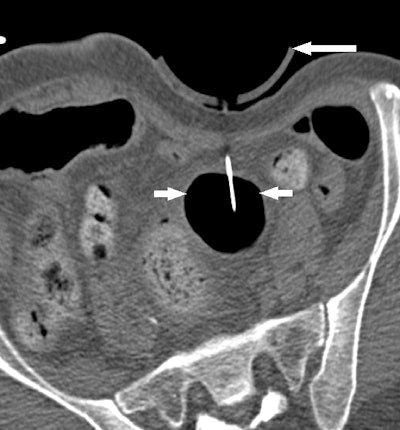

At Brigham, radiologists some time ago modified F-Spoon by cutting a keyhole-shaped notch in the spoon that made it better for guiding needle interventions during CT fluoroscopy studies. By inserting a needle into the keyhole notch, radiologists could compress the abdomen to move bowel loops aside while inserting needles, and they could also keep their hands out of the x-ray beam.

But the proof is in the pudding, so the researchers decided to test their 3D-printed compression paddle by using it in 21 CT fluoroscopy-guided procedures, consisting of 18 biopsies, two abscess drainages, and one liver microwave ablation. They tracked how the device was used and whether the interventional procedure would have been possible without it.

Ultimately, 15 procedures were deemed "questionably feasible" but difficult to perform without the paddle, four were rated as "not feasible" without the device, and two were categorized as feasible without the device but facilitated by the use of it. A particular benefit was the ability to use the paddle to steer the needle by applying pressure against it from inside the keyhole.

Because the goal of the original F-Spoon was to help radiologists avoid radiation while guiding interventional procedures, the Brigham group also measured the amount of radiation dose at the site of the skin incision point for the two abscess drainages, calculating a mean radiation dose of 14.95 mGy. For point of reference, the group calculated a mean radiation dose of 0.31 mGy to the operator's finger, just 2% of the mean dose recorded at the incision point.